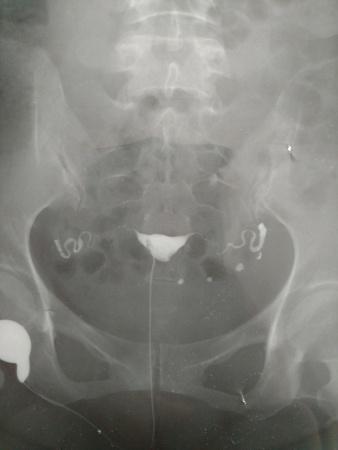

输卵管碘油造影的片子,请帮忙看看,医生意见不一致。

[attach]2075108[/attach]

一位认为输卵管通,但弥散不良,另一位认为通而且弥散也正常。请大家赐教。

很通畅的,图片也很清晰。

通的,两侧都有造影。